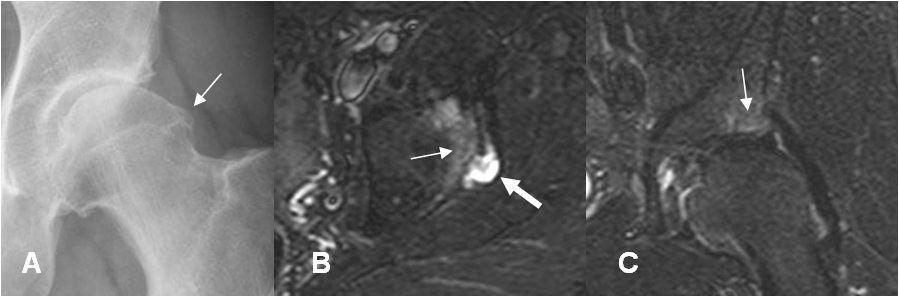

Fig 90. Edema óseo.

A: Rx AP. Prominencia del borde cervicodiafisiario.

B: RM axial y C: RM coronal en STIR. Se aprecia edema óseo del acetábulo, por el microtrauma repetido. Adicional hay quiste paralabral.